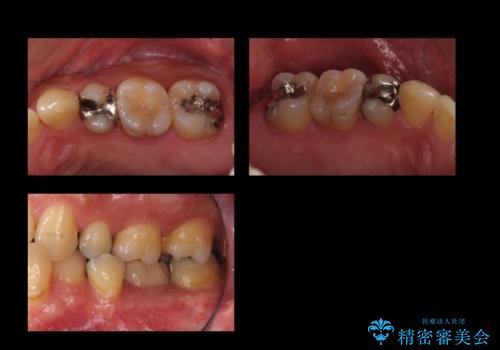

奥歯の詰め物のやりかえ セラミックインレー、ゴールドインレー

- 上の奥歯の詰め物が合っていないため、やりかえを行いました。

- 20万円 内訳 左上56:emaxインレー7万円x2 、左上7:PGAインレー6万円 (税別)費用は治療当時の料金となります

上の一番奥の歯は、一番目立たない場所なので(他人から見えない)、ゴールドインレーでも目立ちません。

セラミックインレーでは割れやすい大きさの虫歯または、歯が薄くなって被せなければいけないような場合でも、金属(ゴールド)は耐久性があり、クラウン(被せ物)にしなくて済みます。